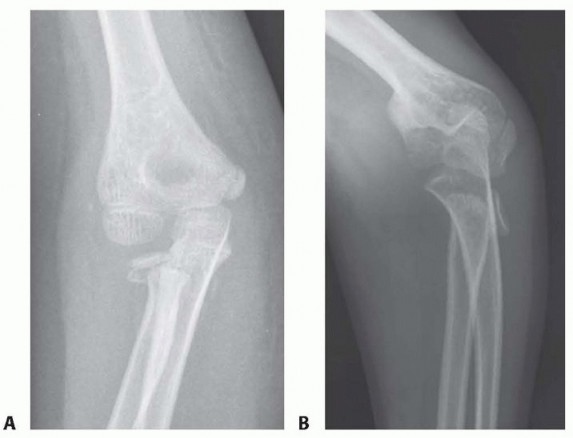

12 MIN READ Closed Reduction and Percutaneous Pinning of Supracondylar Fractures of the Humerus يناير 2023 Read More